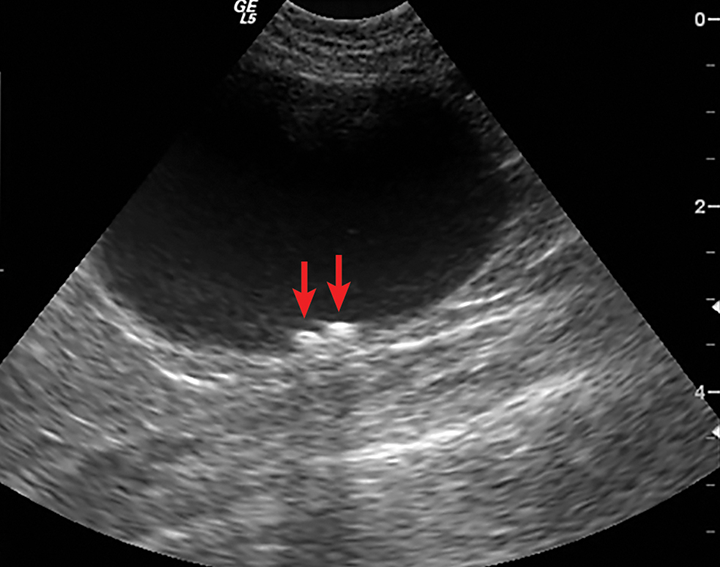

Cat Urine Sample Ultrasound . An ultrasound may be used to accurately locate and sample the urine from the bladder, especially in larger or obese patients. Impossible to obtain a cystocentesis sample, as their bladder never fills sufficiently. Cystocentesis involves inserting a sterile needle, guided by ultrasound, to collect urine from a pet's bladder for urinalysis, helping in diagnosing various conditions. If the bladder is not palpable, but cystocentesis is very desirable (for example, when a urine culture is needed), ultrasound can be used to locate the. This method is used often in dogs, but presents a challenge. In these situations, ultrasound comes into its own.